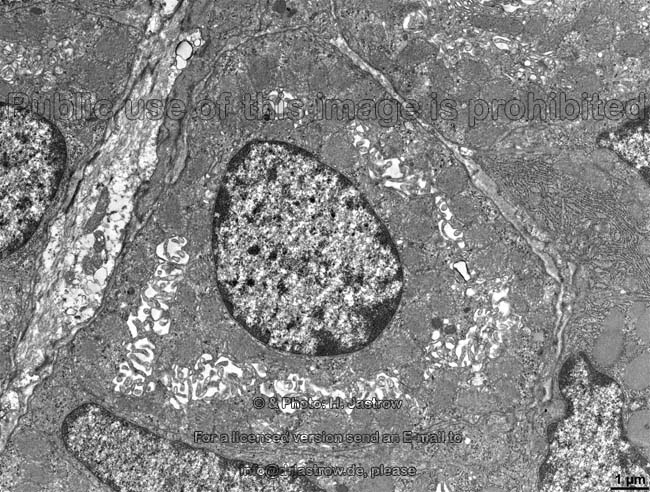

壁细胞(parietal cell)

figure 293-2 gastric parietal cell undergoing transformation

p>壁细胞(parietal cell)又称泌酸细胞(oxyntic cell),在腺的颈,体部